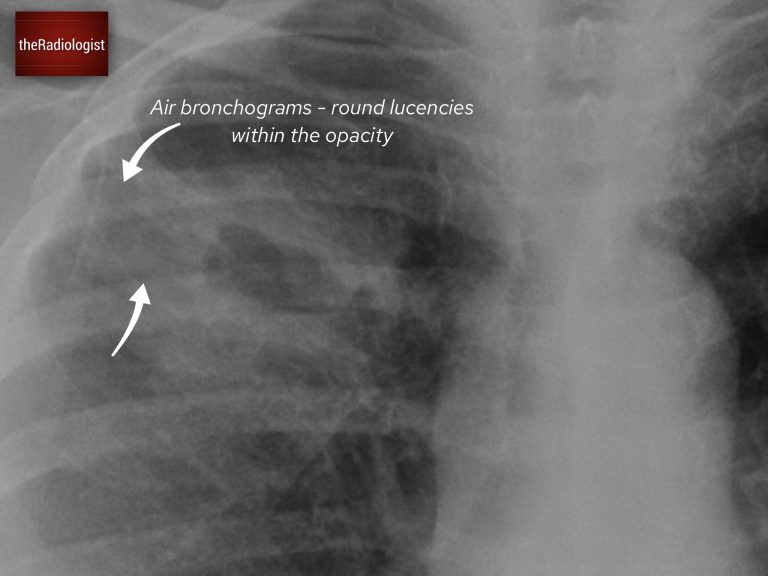

A single cavitating lesion does not always mean lung cancer. In a separate case, a female patient in her 60s presented with a history of cough and fever, along with imaging that showed a cavitating lesion in the right lung. Have a look at the X-Ray below:

PA Chest X-Ray

The X-ray revealed a cavitating lesion surrounded by consolidation. How do we know this is consolidation? Look for air bronchograms: small, round lucencies within the opacity, a hallmark of consolidation.

There are air bronchograms surrounding the cavitating lesion suggesting the presence of consolidation.